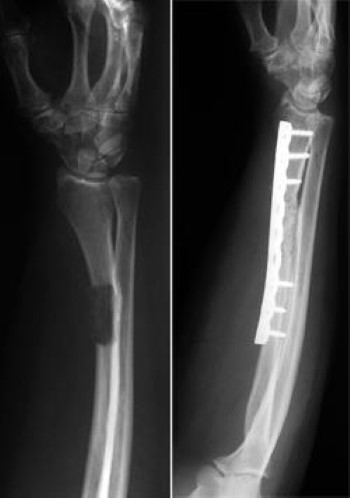

tumor in forearm stabilized with plate and screws

(Left) A large tumor of the ulna bone (forearm) shows up clearly in this X-ray. (Right) The tumor has been removed and the ulna stabilized with a plate and screws.

Reproduced from Schwartz HS, ed: Orthopaedic Knowledge Update: Musculoskeletal Tumors 2. Rosemont, IL, American Academy of Orthopaedic Surgeons, 2007, p 379.